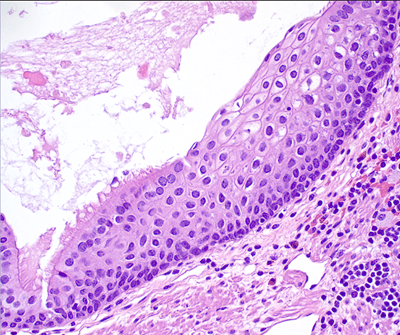

Figure 3. A different area of the cyst lining shows non-keratinizing stratified squamous mucosa with a thinned, but distinct underlying muscularis propria(20x).

Figure 4. This area of the cyst lining shows a clear transition between the ciliated pseudostratified columnar epithelium and the stratified squamous mucosa (40x).